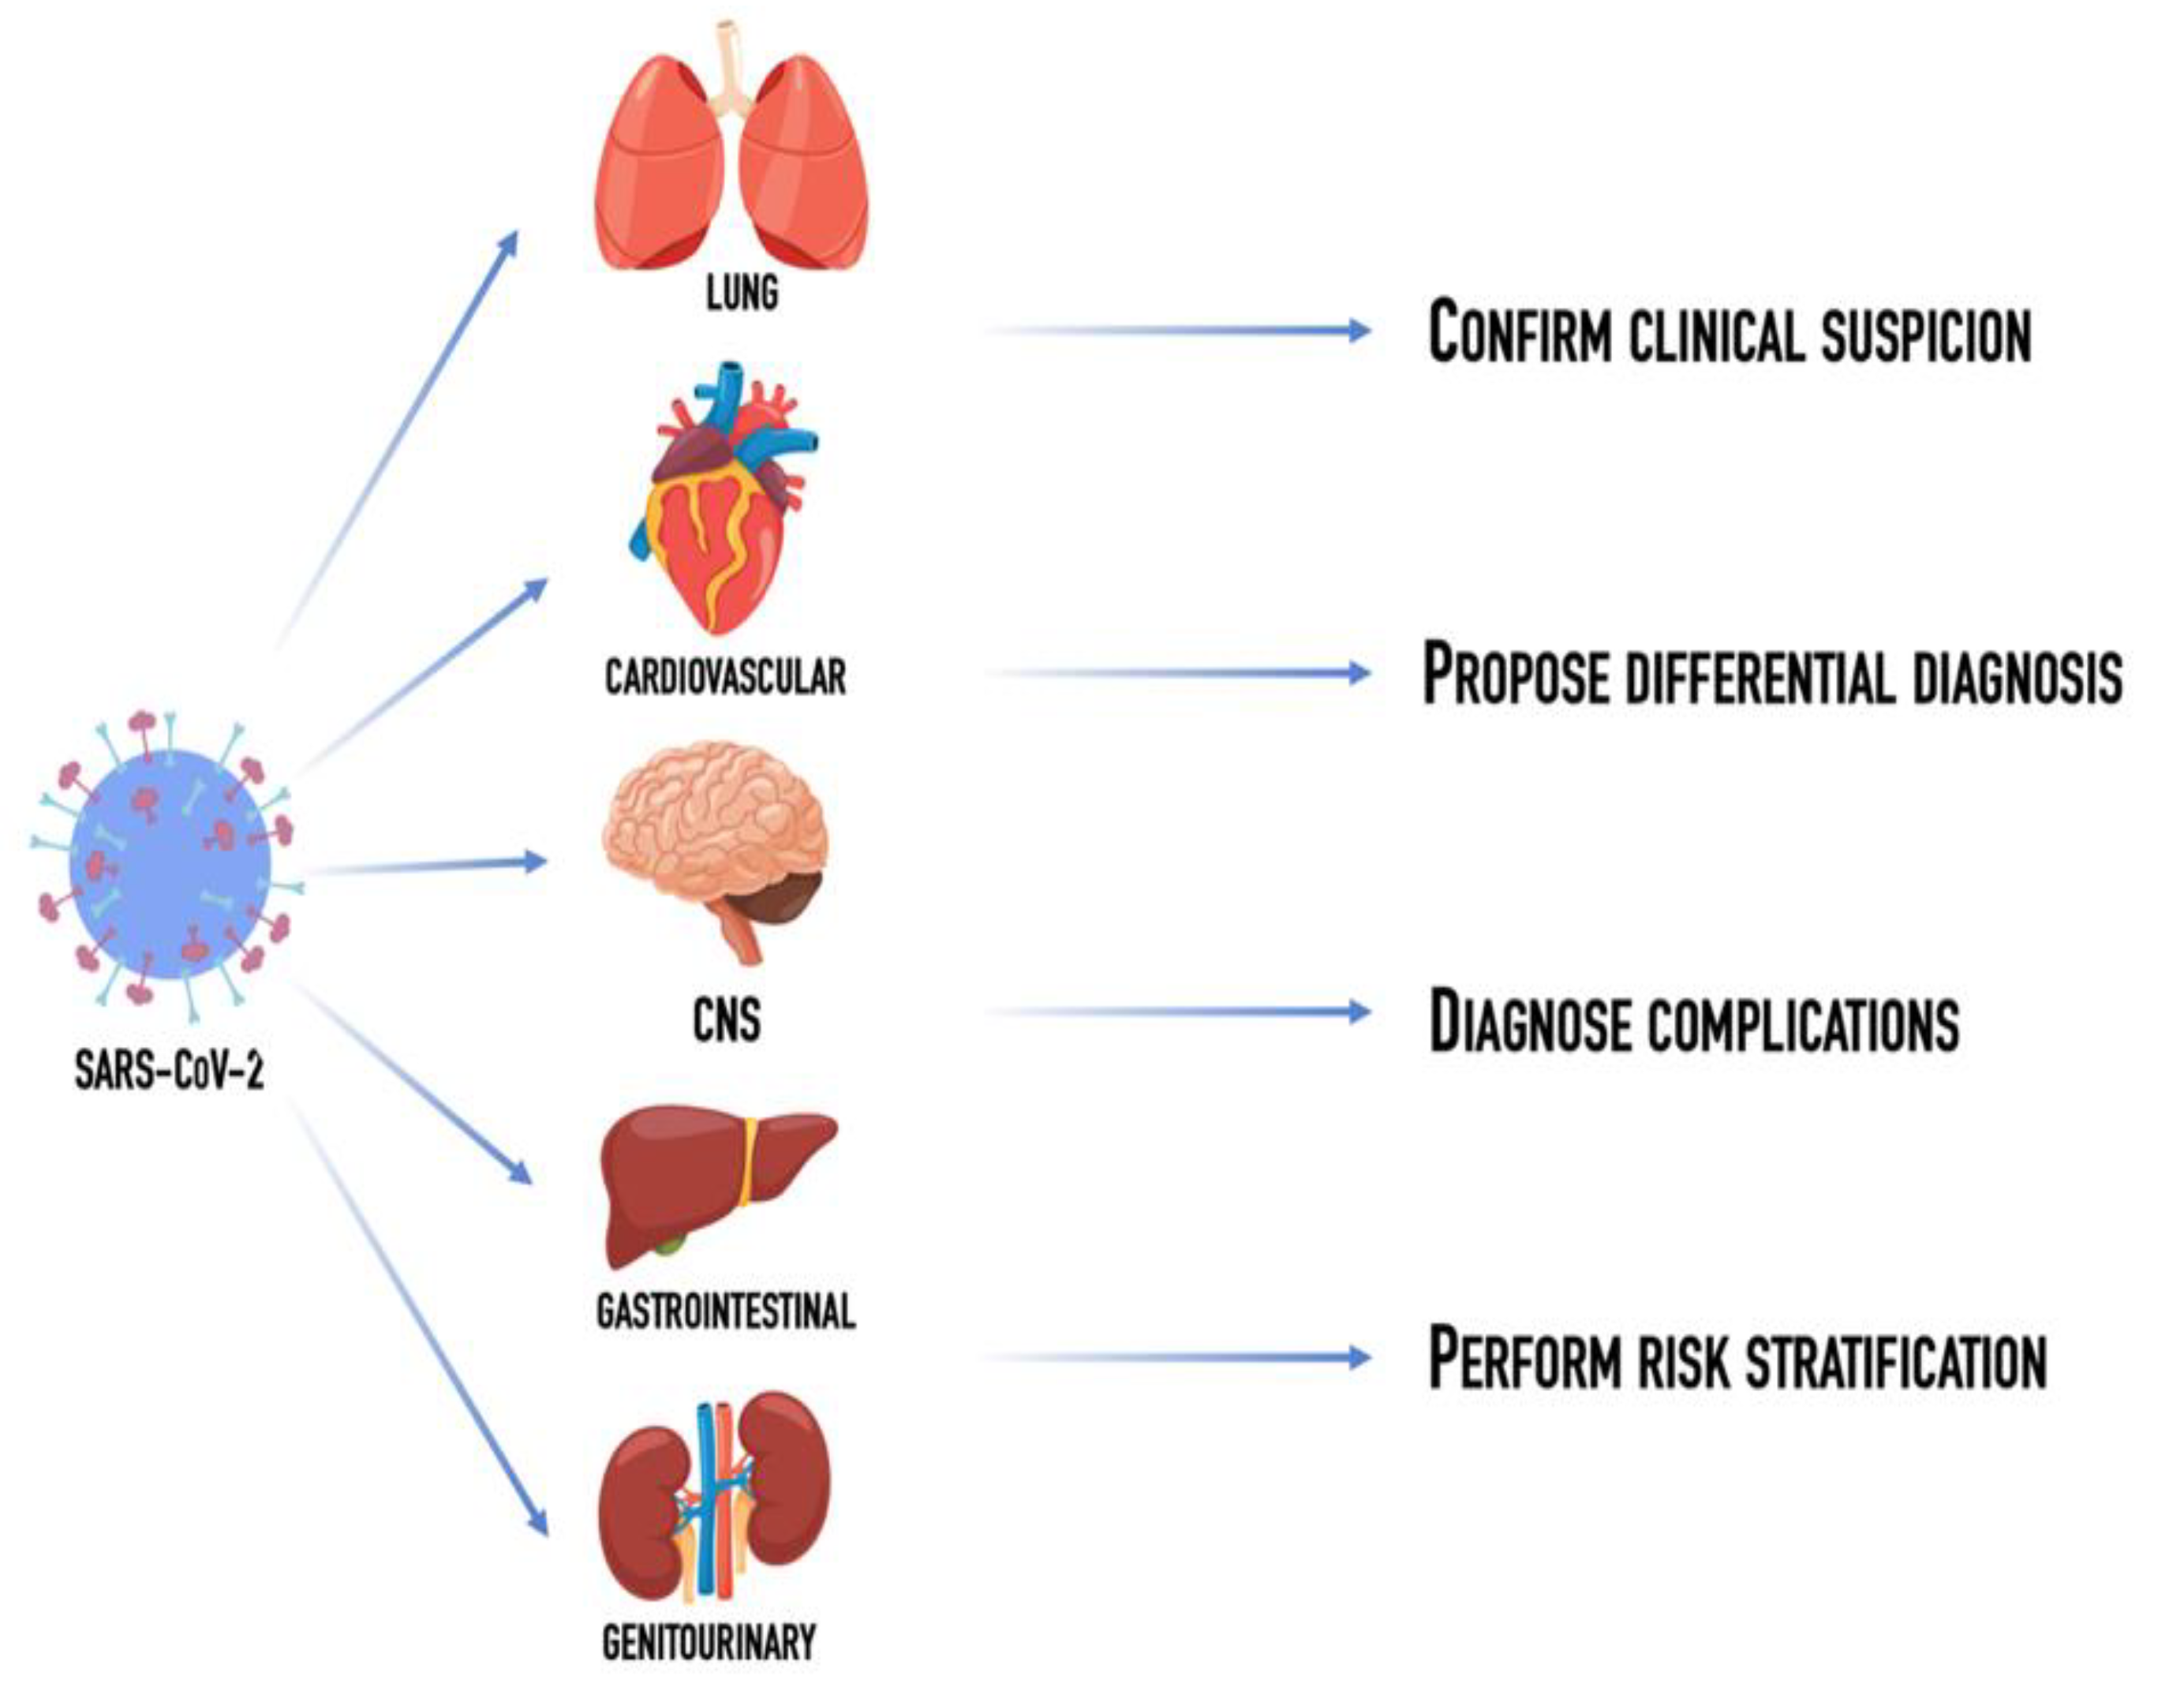

Multiorgan Involvement in SARS-CoV-2 Infection: The Role of the Radiologist from Head to Toe

:1. Introduction

2. Lung Involvement

3. Cardiovascular Involvement

4. Central Nervous System Involvement

5. Abdominal Organs Involvement

6. Genitourinary Involvement